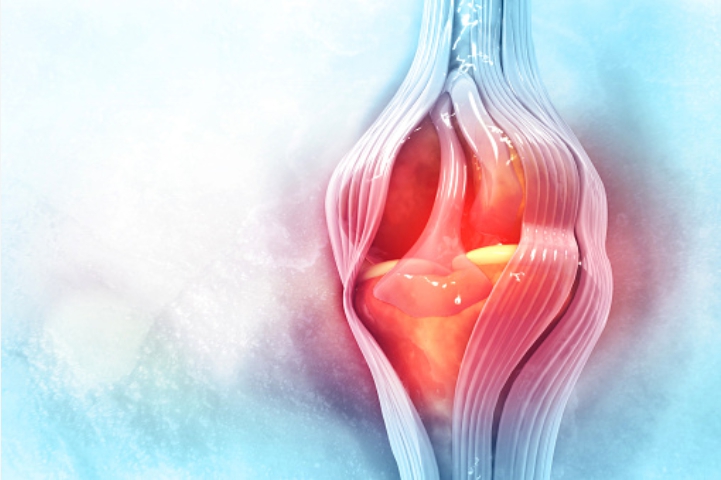

콘드로이친은 우리 몸의 연골을 구성하는 주요 성분 중 하나입니다. 이 콘드로이친의 함량이 저하되면 요통, 관절통, 근육통 등의 증상이 발생합니다.

체내 콘드로이친 성분을 유지하면 관절염 통증 완화와 예방이나 연골 건강에 도움이 됩니다. 콘드로이친은 천연 소염제로써 연골이 약화되는 것을 억제해 주는 역할을 합니다.

콘드로이친은 연골 손상을 막을 뿐만 아니라 손상된 연골의 주요 성분인 연골세포를 재생시켜 연골 기능을 향상해 주는 역할을 합니다. 연골 손상으로 고통을 호소하는 사람들에게 도움이 됩니다.